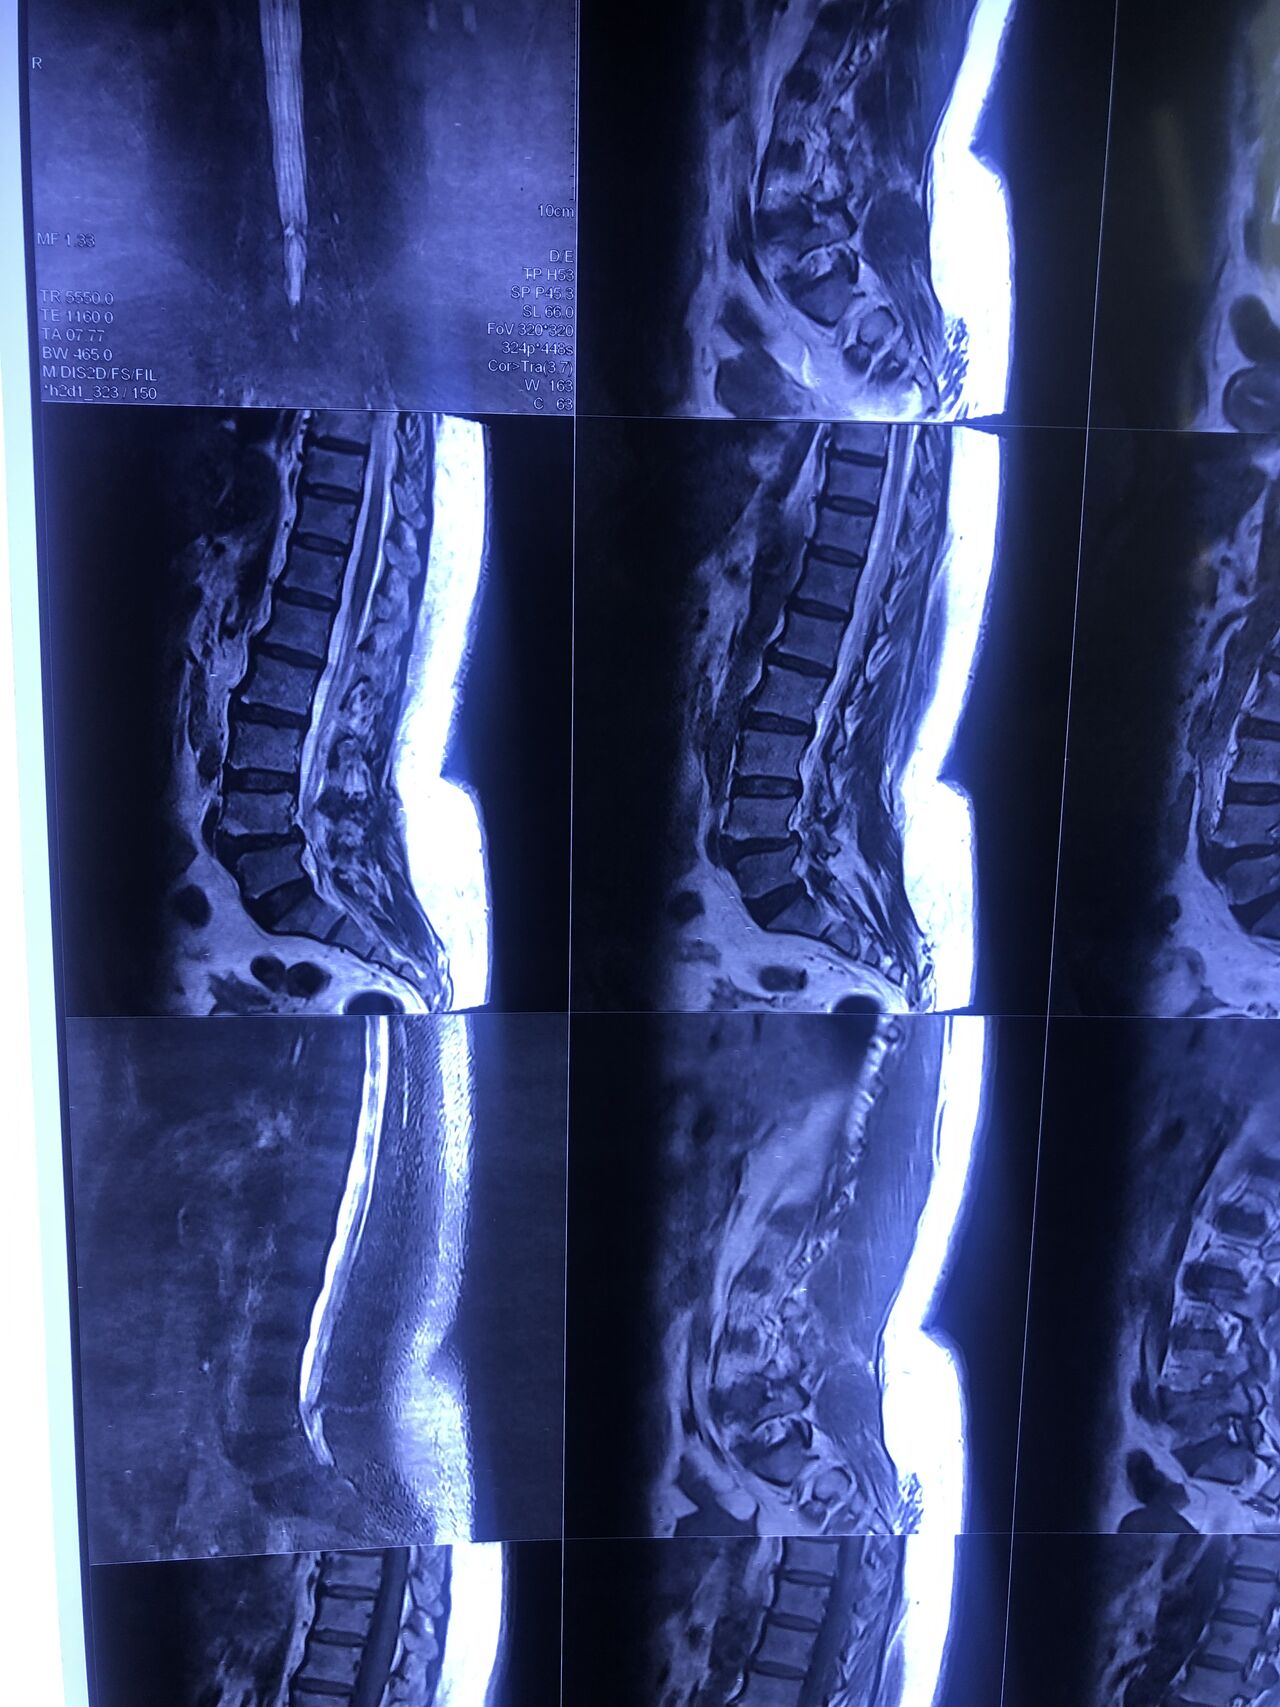

46 years old female patient presented to my clinic yesterday june 1/2025 with LBP and radicular L leg pain for several months which hasn’t responded to physio 2 neurosurgeons have visited her and didn’t suggest any surgery Neurological exam was unremarkable please see her mri/ emg/ncv and her huge tarlov cyst and possible L IVF L4-5 hyperbulge I ordered sacrum mri and ct scan and new emg/ncv and asked her with her sacral Ct scan and MRI first sees another two famous neurosurgeons and see if that large cyst is the reason for her pain if not i can work on her L4-S1 area Do you think her radicular pain can originate from her large cyst in sacrum? Do you consider surgery and removing her sacral cyst?